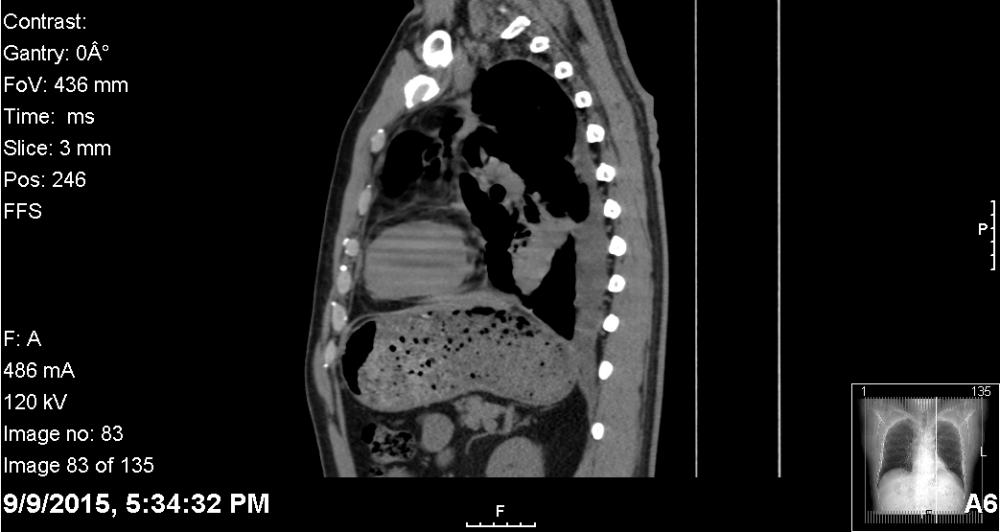

九月九日再次抽出一升半褐色胸水。接着做了胸部CT。第二天收到报告:左肺下叶占位性病变並向前上方沿胸膜延展,左肺可见散在胸膜结状物。(There is a 4.6 x 4.2 x 3.2 cm left lower lobe mass like opacity with a thick band extending anteriorly and superiorly along the pleura. Scattered pleural nodularity is seen throughout the left lung)

附件:第一次CT三维截图,非专业勿看